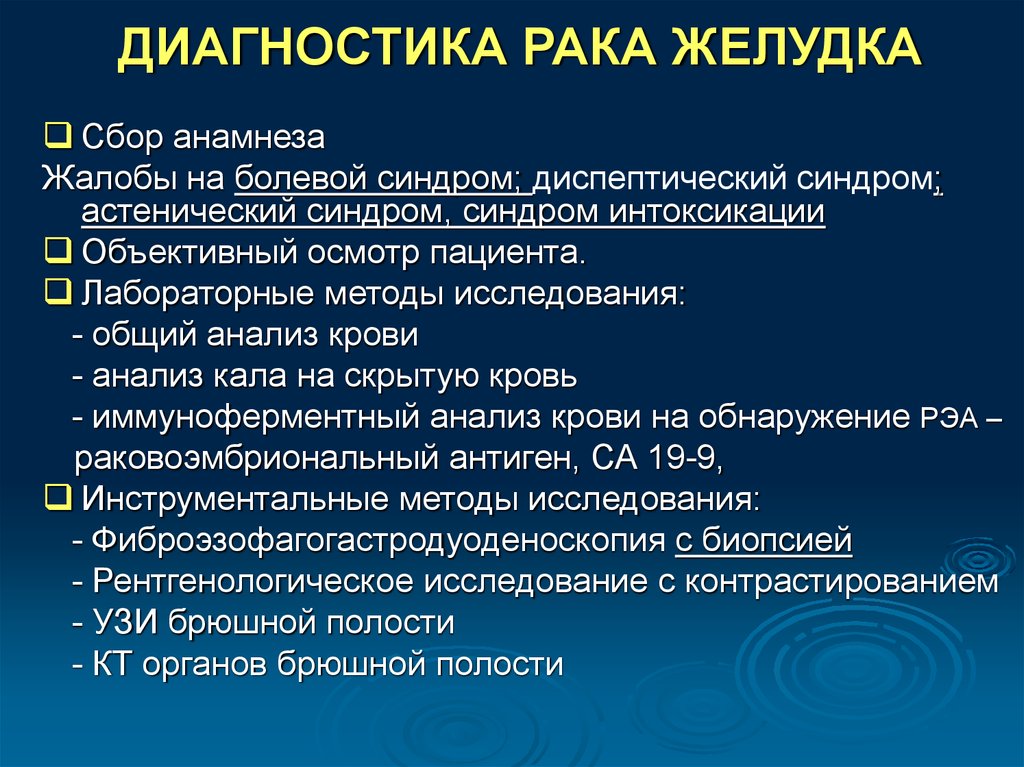

Методы исследования при опухоли головного мозга. Дополнительные методы исследования опухолей головного мозга. Диагноз кт с опухолью головного мозга. Дополнительные методы исследования при опухолях головного мозга. Диагностика ра а желудка. РВК желудка дипгностика. Иагностика рада желудка. Методы диагностики в онкологии.

Диагностика ра а желудка. РВК желудка дипгностика. Иагностика рада желудка. Методы диагностики в онкологии. Опкхолльлголовного мозга. Новообразование в головном мозге. Злокачественная опухоль головного мозга.